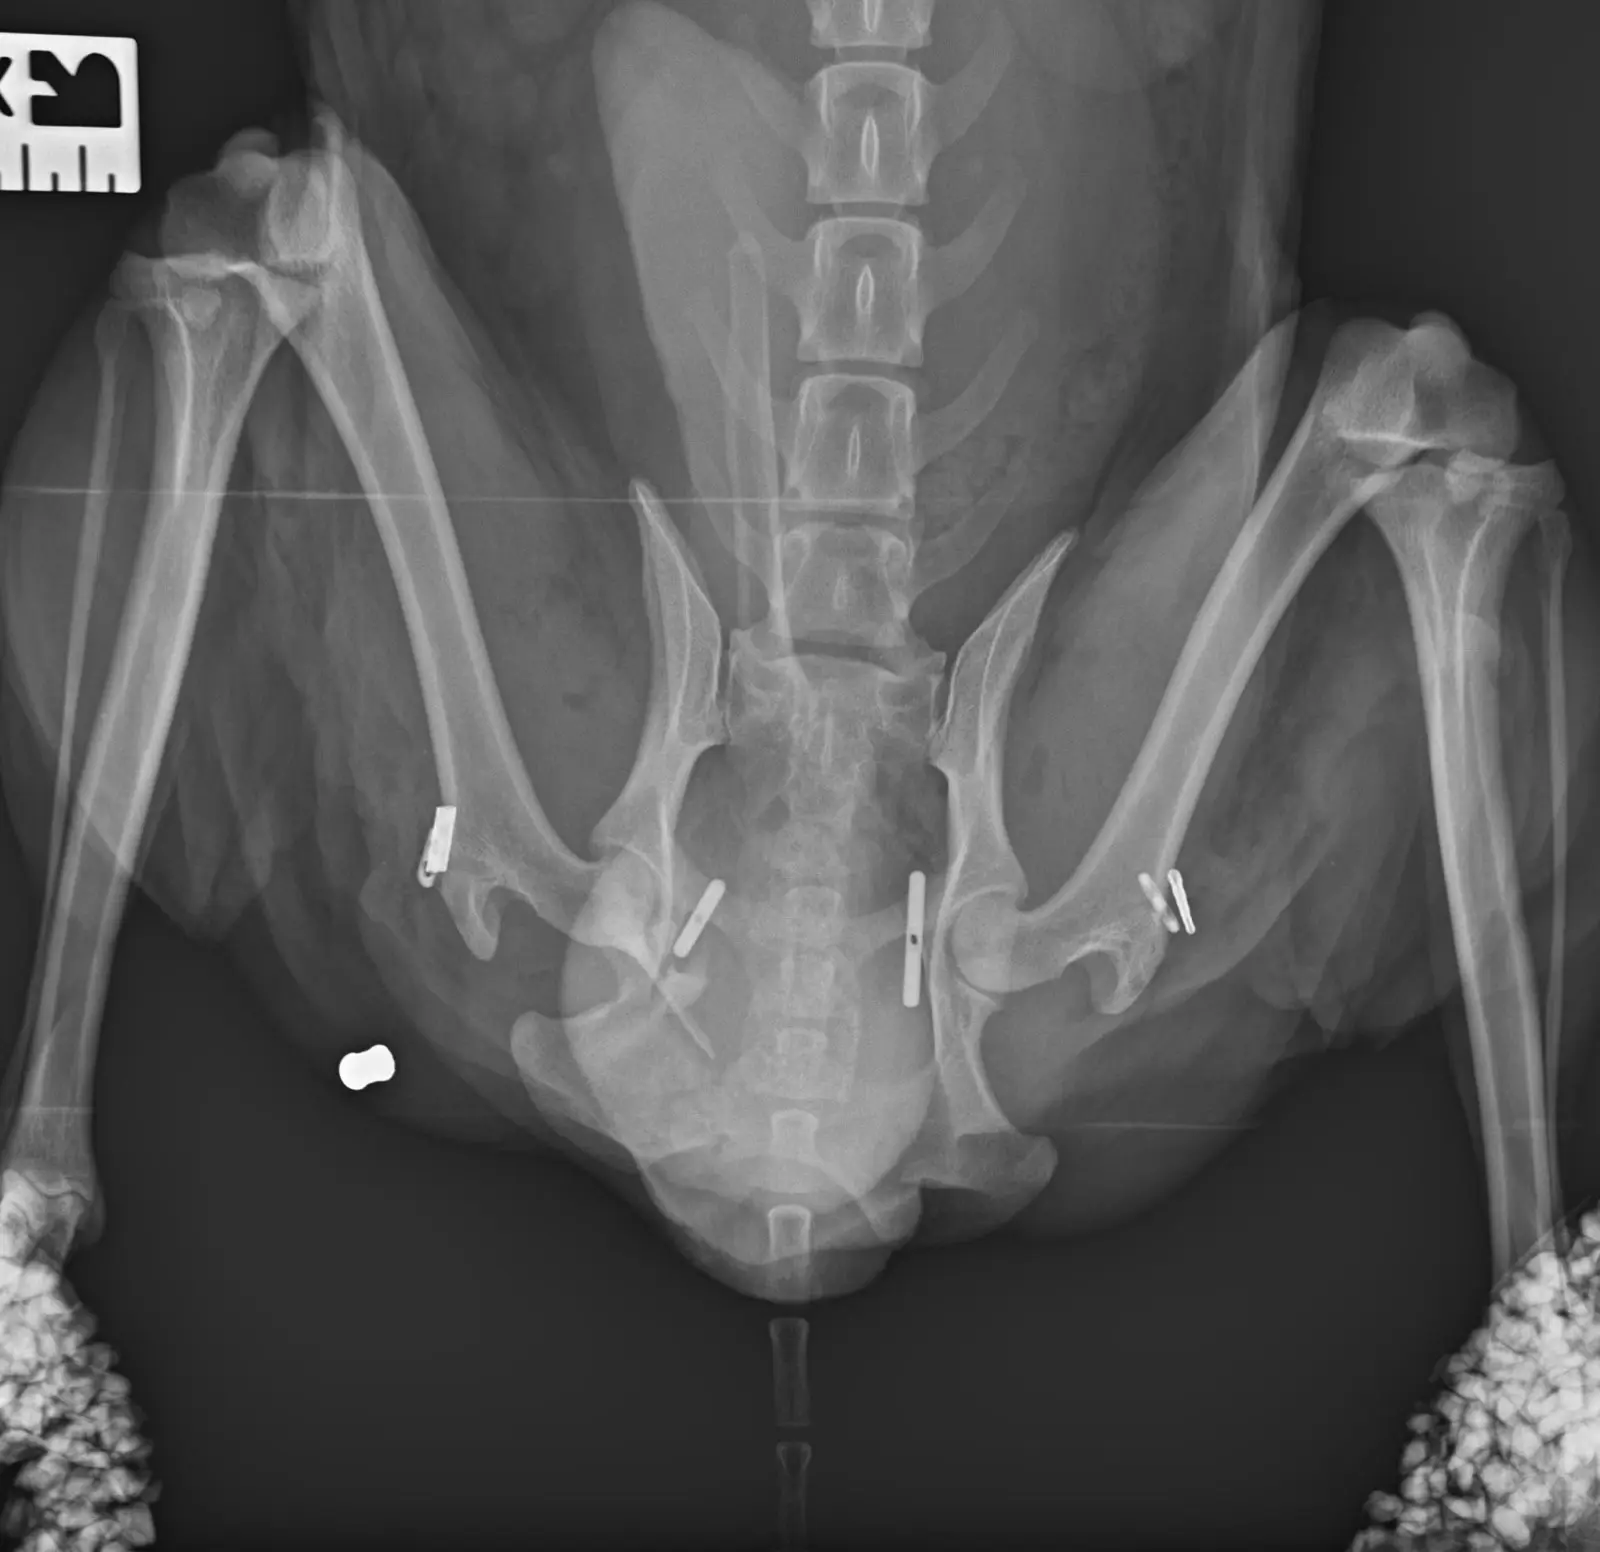

Моля ,който може да помогне !На 29.10 беше първата му операция  за открита фрактура на предна дясна лапа оператор  е  д-р Йордан Стоянов ортопед и на 31.10  беше втората много тежка операция на множество фрактури на таза и за луксациите на двете тазобедрени стави

Please who can help !On 29.10 was his first surgery for open fracture of front right paw operator is Dr. Jordan Stoyanov orthopedist and on 31.10 was the second very severe surgery for multiple fractures of the pelvis and for the luxations of both hip joints